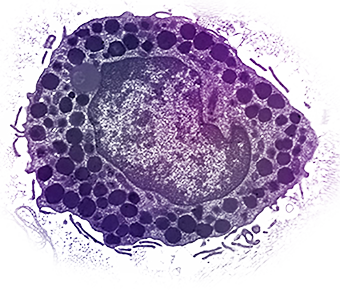

Mast cells are "master regulators" of the immune system. They come from bone marrow and go into all tissues of the body. Each mast cell contains secretory granules (storage sacs), each containing powerful biologically active molecules called mediators. These can be secreted when mast cells are triggered, leading to allergic and inflammatory diseases.

View "Mast Cells — Visual Perspectives"